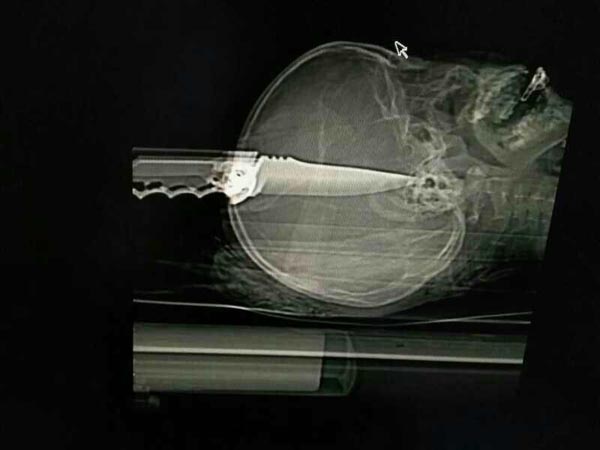

经查,受害人肖某(男,9岁,系隆回县横板桥镇中心小学二年级学生)下午放学走出校门时,被犯罪嫌疑人张某辉(男,31岁,隆回县南岳庙镇人,系该学校自聘保安)从后面用单刃折叠刀直刺头部倒地。据张某辉供述,其与受害人肖某并不认识,因案发当天吸食毒品,系吸毒致幻后作案。经检查,张某辉尿液呈阳性,民警随后在其家中搜出吸毒工具。